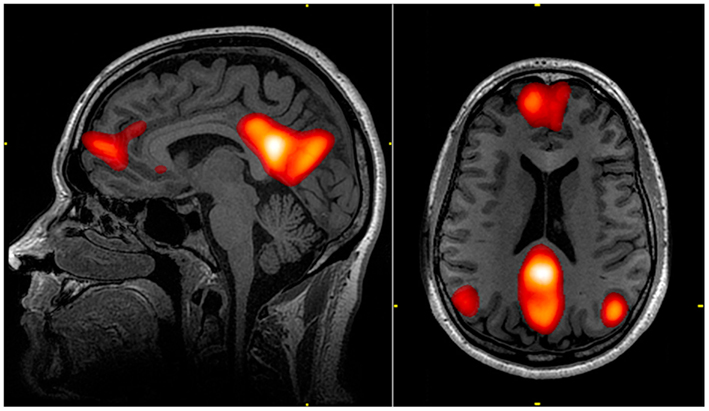

Из дофаминового дефицита вытекает ещё одна конкретная проблема. В мозге есть так называемая Default Mode Network (DMN) [6] — сеть пассивного режима работы мозга. Она активна, когда вы ничего не делаете: мечтаете, вспоминаете прошлое, залипаете в окошко, пока едете на работу. В норме, когда вы садитесь за работу, DMN подавляется и мозг переключается в рабочий режим.

Активные зоны Default Mode Network, подсвеченные на фМРТ-сканировании. Wikipedia, CC BY 3.0 (Walter Reed National Military Medical Center)

При СДВГ это переключение ломается. DMN продолжает фонить, вклиниваясь в рабочие процессы и вызывая те самые «провалы внимания», когда ты вроде смотришь в монитор или слушаешь не очень (или даже очень) интересного спикера на конфе, а мысли уже где-то далеко [3]. Исследование в Nature Neuroscience подтвердило: кратковременные провалы внимания напрямую связаны с тем, что DMN не деактивируется как надо [4].